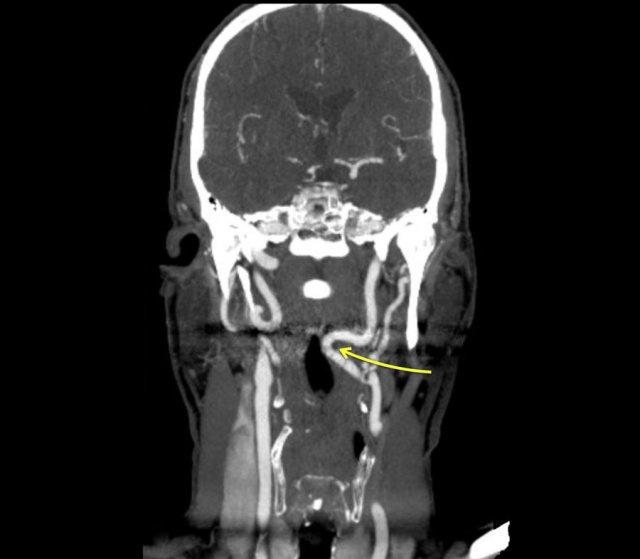

Tiếp tục với hình ảnh CT của bệnh nhân này.

Vết lõm của hầu miệng do động mạch cảnh trong bị dài ra (mũi tên xanh dương). So sánh với vị trí của động mạch cảnh bên trái

Hình ảnh CT cho thấy vết lõm nhẵn của hầu miệng bên phải là do động mạch cảnh trong bị dài ra gây nên.

Đây quả thực là một trường hợp hiếm gặp, trong đó trên nghiên cứu huỳnh quang ban đầu nghi ngờ có khối u ở xoang lê.

Cuối cùng phát hiện một tổn thương trong hầu miệng và một tổn thương chèn ép thành từ bên ngoài ở mức cao hơn.

Do các tổn thương này, thuốc cản quang đi qua hạ hầu bất đối xứng, giả tạo hình ảnh tổn thương ở xoang lê.

Đây là một bệnh nhân khác với động mạch cảnh trong bị dài ra.

Bệnh nhân này có triệu chứng khó nuốt và khi thăm khám thấy một cấu trúc đập theo nhịp mạch trong hầu miệng.

Đây không phải là phát hiện hiếm gặp.

Vì vậy, trước khi thực hiện sinh thiết ở vùng này, cần đảm bảo rằng đó không phải là động mạch cảnh.